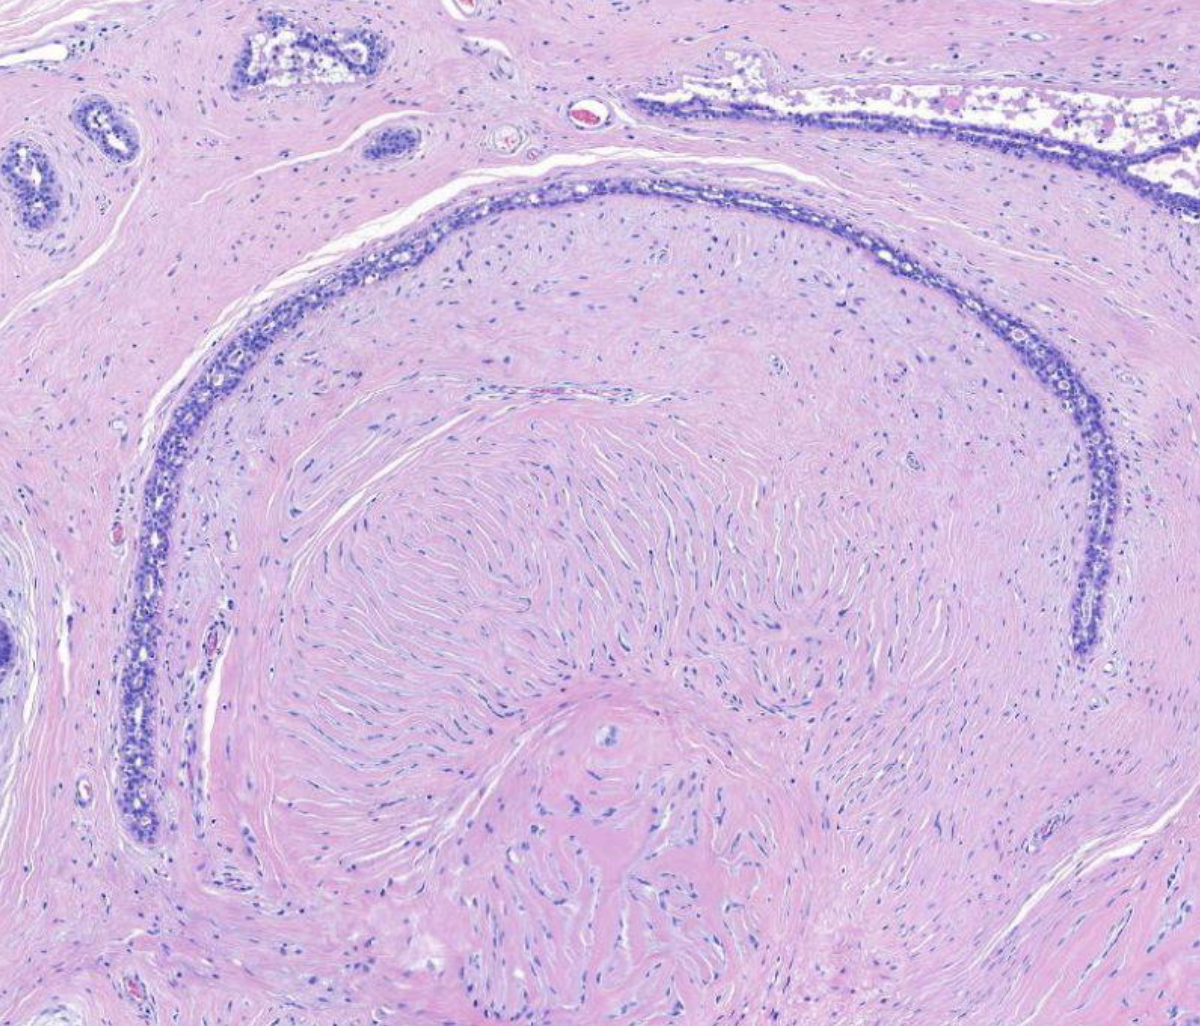

Diagnose?

Pleomorphes Speicheldrüsenadenom = BENIGNE

80% in der Parotis -> nicht destruktiv, nicht invasiv, nur verdrängend

v.a .Parotis, benigne, aufgebaut aus bindegewebiger Kapsel und epithelialen und mesenchymalen Gewebe (v.a. Knorpelgewebe)